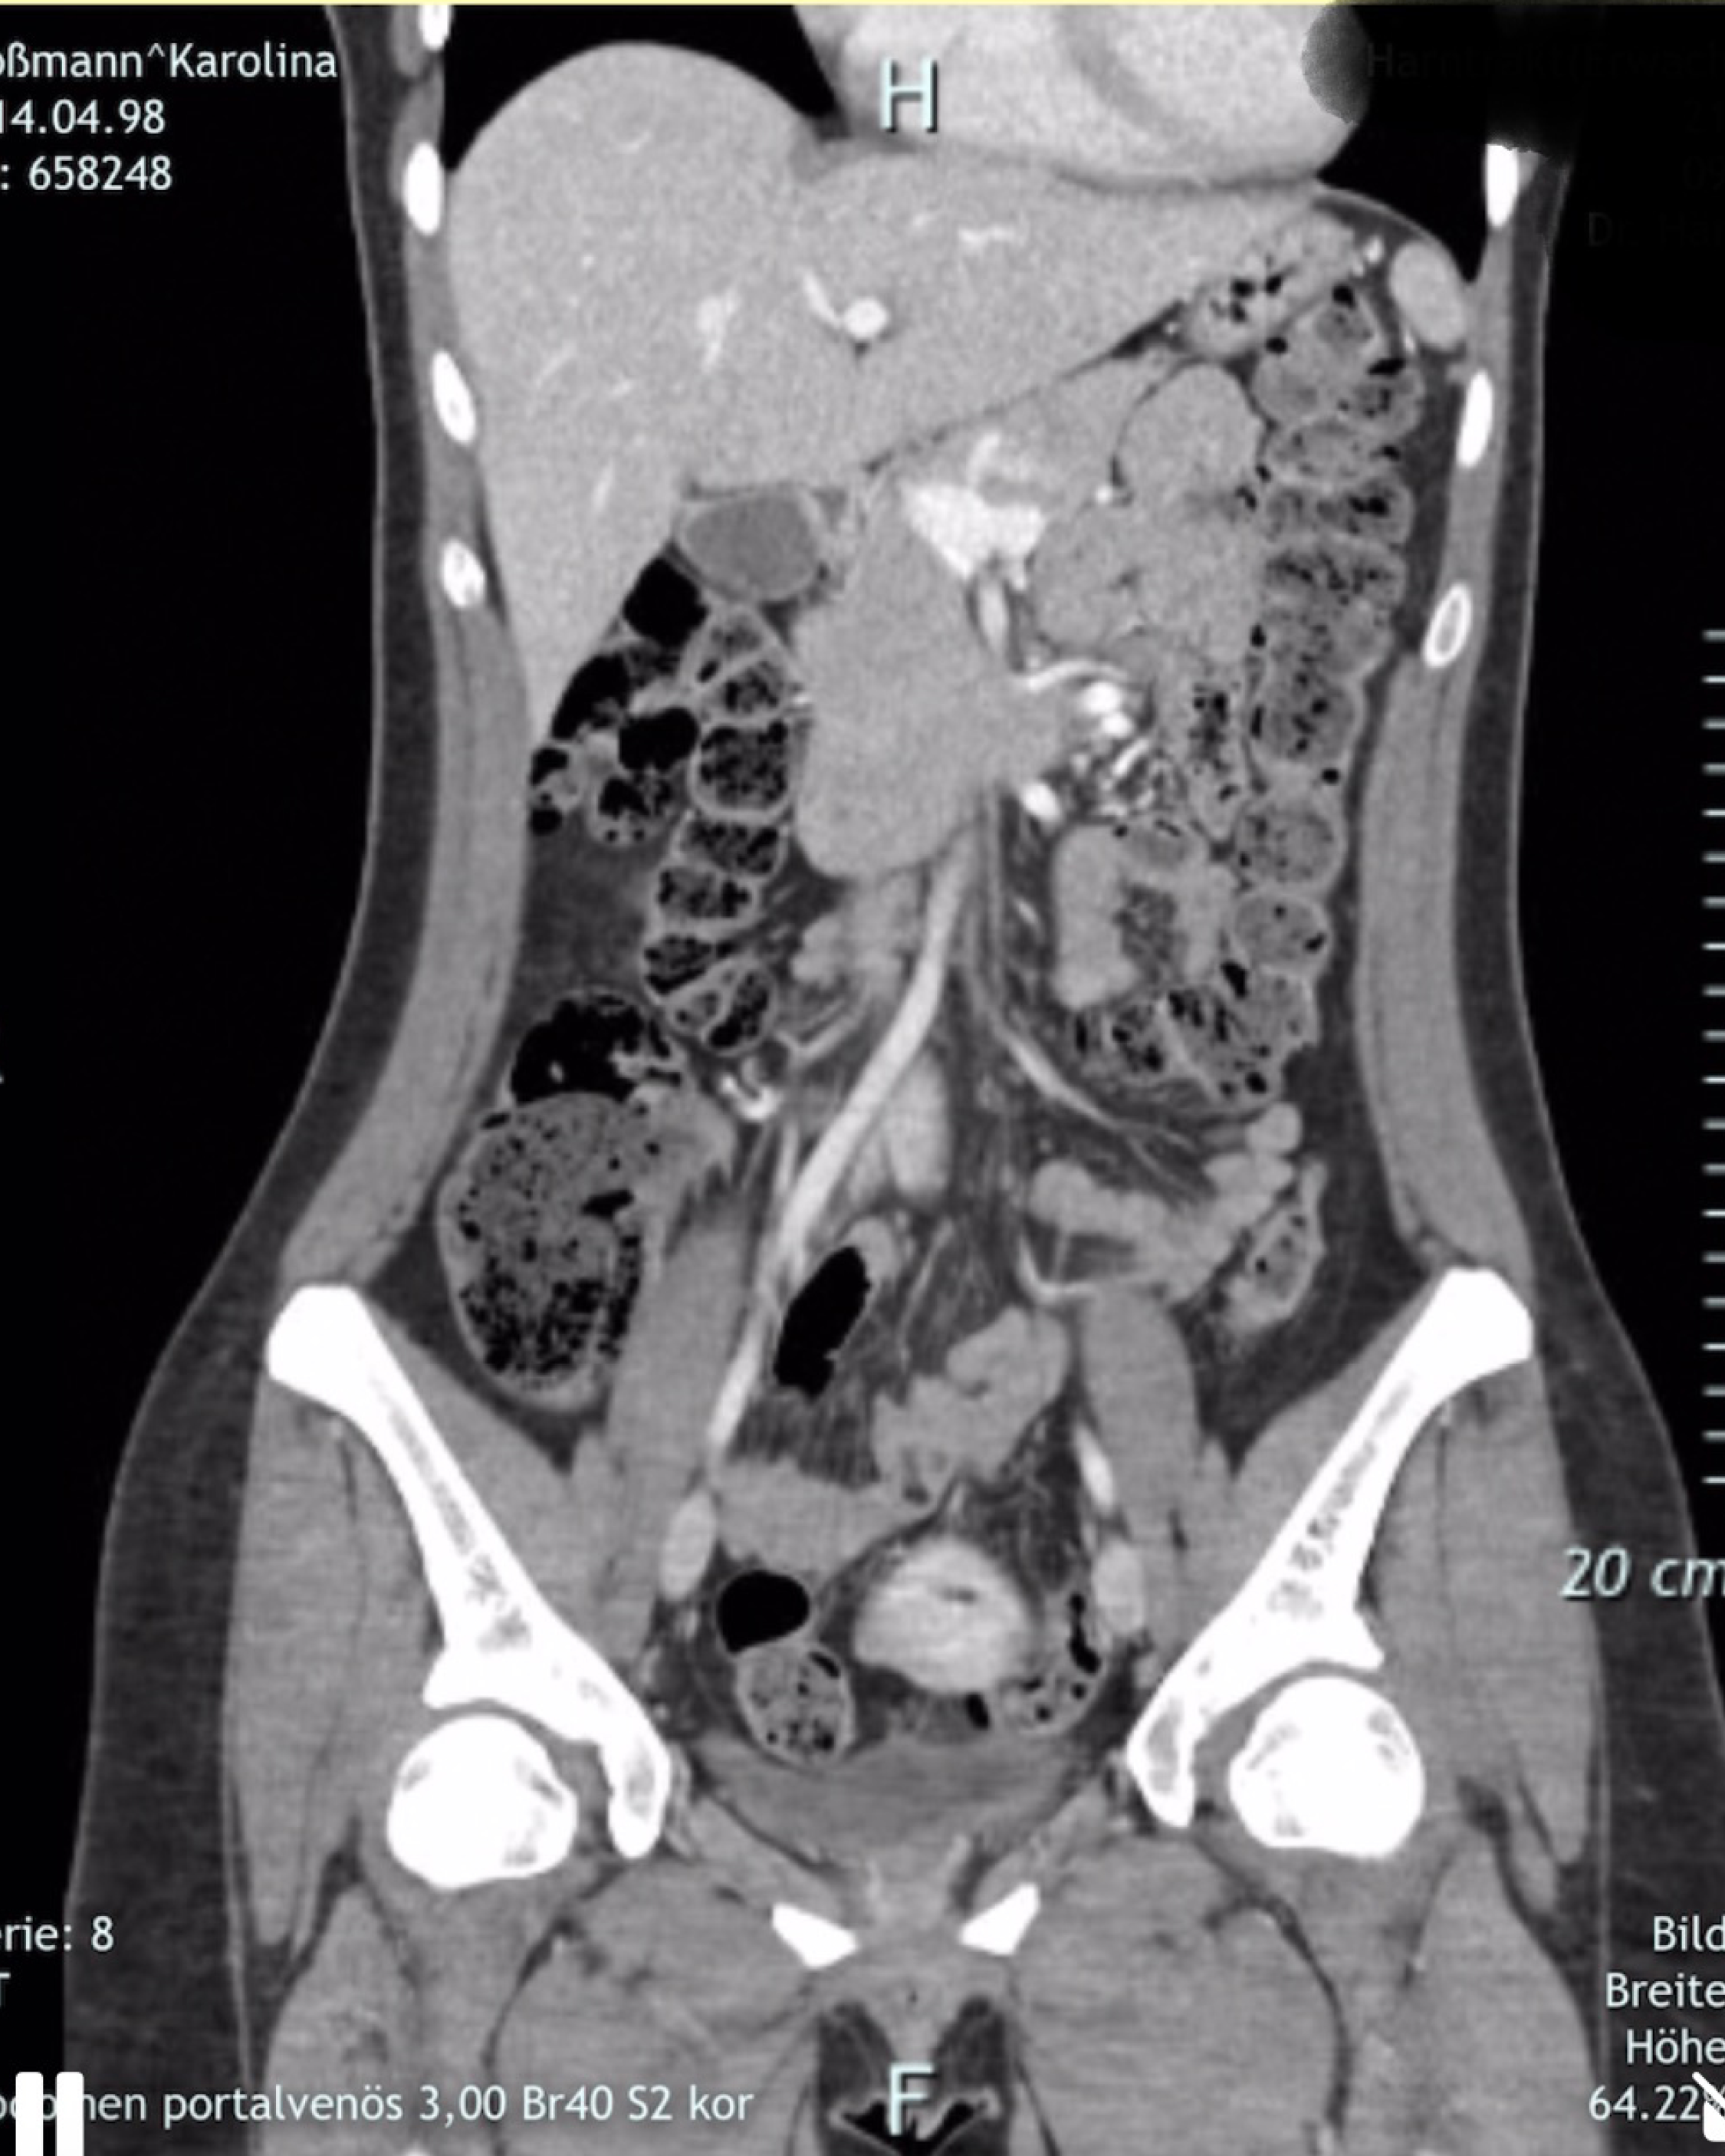

Von hinten durch die Brust ins Auge:

Karolina Koßmann arbeitet ohne Skizzen und ohne Konzepte. In einem „hedonistischen“ Prozess verfolgt sie assoziative Ketten und changiert zwischen bewussten Entscheidungen und dem Zulassen von Unvorhergesehenem. Die affekthafte Unmittelbarkeit in ihrer Arbeit resultiert in direkten Motiven, aber auch in schrägen und irritierenden Verschiebungen und Brüchen. Sie verwendet bekannte Motive und Assoziationen, eignet sich diese an, überformt und verfremdet sie. Die Arbeiten flirten mit Kitsch und Pathos, ohne beides zuzulassen. Koßmann will mit ihren Bildern weder analysieren noch bewerten. Stattdessen geben sie Zugang zu einer Faszination und einem Prozess – direkt, emotional und persönlich.

Von hinten durch die Brust ins Auge beschreibt einen unnötig komplizierten Zugangsweg. Zugleich ist es dieser unmögliche Schuss, der präzise den ganzen Körper durchdringt. In einem CT wird dieses Durchdringen plötzlich möglich und leicht. Bilder von Körpern bauen sich Schicht für Schicht auf und ermöglichen Beobachtenden einen voyeuristischen Blick ins Innerste. Der Wunsch, durch die Schichten zu dringen und hinter die Oberfläche zu blicken, entsteht sowohl in der Malerei als auch in der Beziehung zum Objekt der Begierde. Doch weder die Leinwand noch das andere lassen sich komplett durchdringen oder verstehen. In ihrer Arbeit nähert sich Karolina Koßmann Körpern, Objekten und Ideen an, die sich immer wieder verflüchtigen. Wie nah können wir Werken und Sehnsüchten wirklich kommen?

Text: Samuel Herrmann